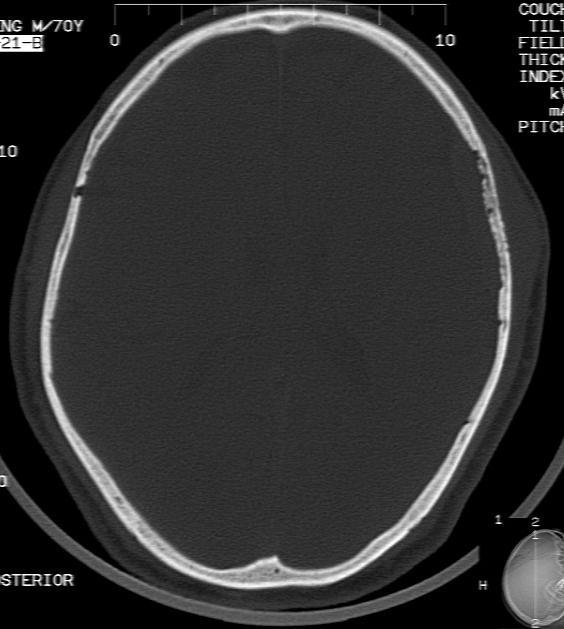

m70y, 2个月前发现左颞部有'包'隆起,近来自觉增大,无外伤无任何不适症状而就医,触诊包块质地较硬无移动无波动无皮温升高,胸片示右上肺陈旧结核....,ct扫描见左颞骨翼板局部内外骨板骨质破坏,似筛孔状,外板侧有骨膜线状增生,伴局部软组织丘状肿块,内板下梭形肿胀硬膜增厚翘起......颅内脑无异常.考虑骨良性病变 1.低度骨感染.   2.嗜酸性肉芽肿. 3.不排外骨结核...建议其穿刺活检,但患者失踪,追踪到结果定将公告.请大家分析.

左颞骨内板不光滑,密度减低,内板下可见新月形的软织密度影。脑实质轻度受压,外板外见膨胀形稍高密度影。考虑嗜酸性肉芽肿。建议增强扫描

考虑为骨感染,颅内脑实质受压,颞部头皮软组织肿胀

骨质密度不均,骨质两旁均有软组织影,考虑嗜酸性肉芽肿可能性大,同时也不能除外转移瘤。

除了以上的诊断,大家不考虑转移瘤吗,病人有陈旧结核,合并瘢痕癌呢,并发颅骨转移,肺癌发生骨转移的几率要比其它恶性肿瘤大的多,虫蚀样的骨质破坏就是良性病变吗,我考虑转移瘤。